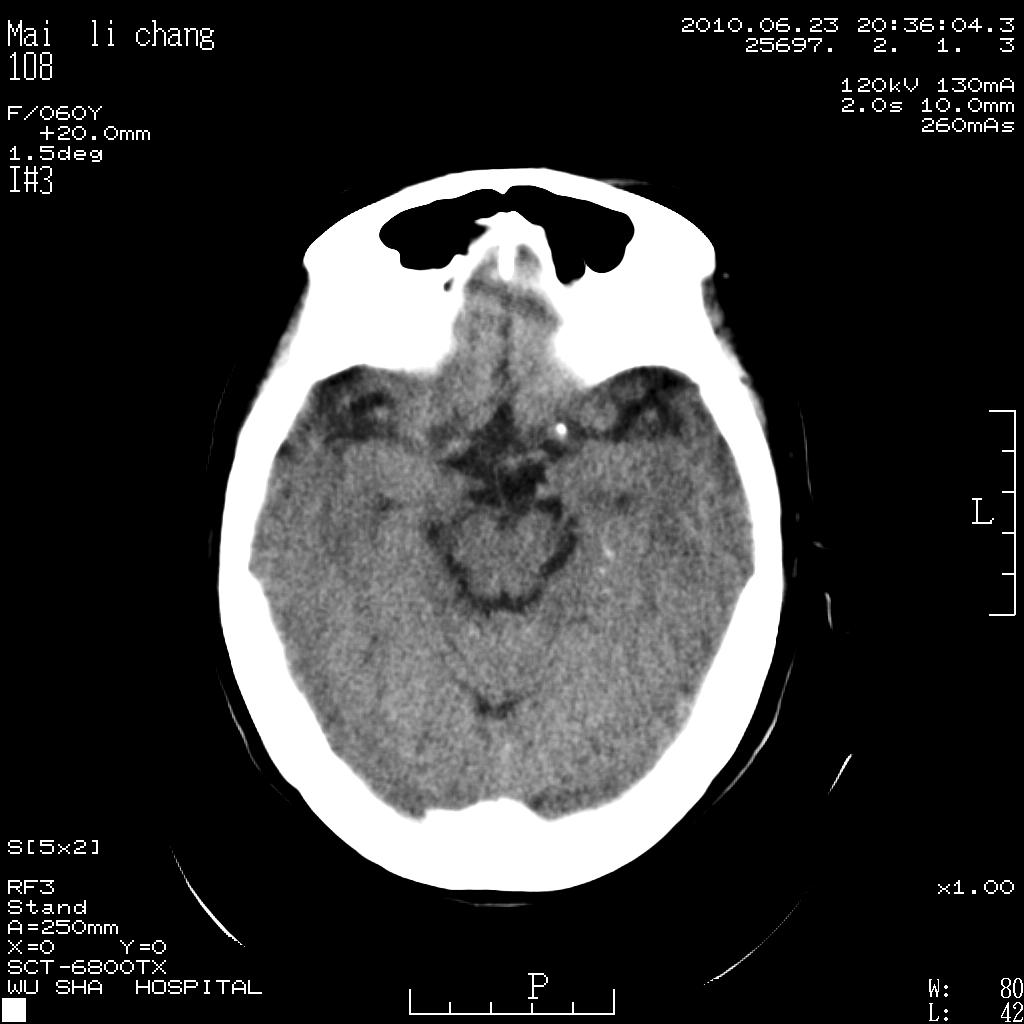

女性,60岁,右手无力一天

脑梗塞?并皮层下动脉硬化性脑病?还需要考虑什么?请大家指导,先谢了。

考虑左侧基底节区脑梗塞。

从提供的临床资料及影像检查不考虑皮层下动脉硬化性脑病。

左侧基底节区及放射冠区多发脑梗塞。

左侧基底节区及侧脑室旁多发脑梗塞

2.左侧基底节区可见片状低密度病灶。

意见考虑脑梗塞。

左侧基底节区大面积梗塞,必要增强扫描协诊

左侧基底节及放射冠区脑梗塞。